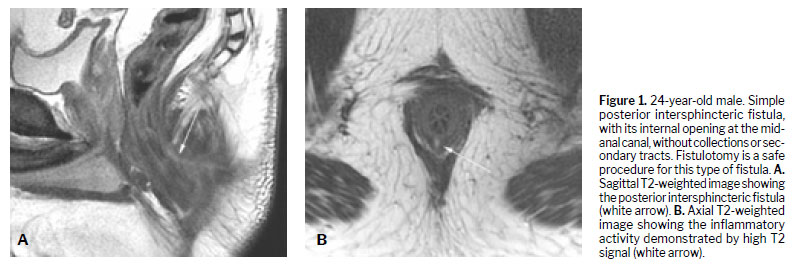

Various techniques can be used for the morphological evaluation of the fistula and its relationships with pelvic and perianal structures, including X-ray fistulography, computed tomography, endorectal or transrectal ultrasound, and MRI(11). Surgeons have access to 3D reconstructed endorectal ultrasound as a tool that can be used in the office and in outpatient settings, making it helpful in characterizing fistulas and anorectal abscesses, identifying the internal opening, and determining the main tract of a fistula. Among the various imaging modalities, MRI is the method of choice for studying anorectal fistulas, because it is superior for characterizing secondary tracts(2,6). Evidence from observational studies summarized in a narrative review has shown that MRI-guided surgery can reduce the likelihood of recurrence by approximately 75%, mainly by allowing precise preoperative identification of fistulous tracts and secondary extensions that might otherwise go undetected(5). Prospective observational studies suggest that this imaging method, used preoperatively, modifies surgical strategy in approximately 10% of patients with primary fistulas and 21% of those with primary, secondary, or Crohn’s disease-related fistulas(1). The benefits are even greater for sphincter-preserving procedures(5). Certain aspects of fistula morphology favor certain surgical procedures, whereas other procedures are contraindicated by specific morphological characteristics(7). Several studies have discussed which are the most relevant characteristics to be described in MRI reports in the evaluation of anorectal fistulas, as well as the best form of presentation, such as structured reporting, to improve understanding on the part of the attending physician(2,5,12). However, in cases of complex anorectal fistulas, reports can still be challenging to interpret for adequate surgical planning(3). In recent years, 3D modeling has gained space as a promising tool to aid in surgical planning(3). Figures 1–5 demonstrate MRI-based strategies in the evaluation of perianal fistulas, highlighting traditional 2D sequences as well as 3D reconstructions.

(6): simple fistulas, for which fistulotomy is a safe procedure with high cure rates and no postoperative continence problems; and complex fistulas, in which there is significant involvement of the anal sphincter, associated with higher rates of recurrence and risk of incontinence, which should be treated exclusively with sphincter-preserving techniques.

(6).Among the possible surgical treatments, fistulotomy is the procedure most frequently performed for simple fistulas, which account for approximately 30–50% of cases, with a cure rate of approximately 95% when all tracts are treated. In general, fistulotomy results in a reliable cure and reasonable patient satisfaction when 2 cm of the most cephalic EAS is preserved, and it is generally used in intersphincteric and low transsphincteric fistulas

(1,6). However, fistulotomy carries a high risk of fecal incontinence, especially when performed for complex fistulas